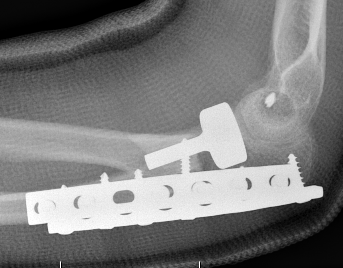

Olecranon plate + ORIF Type II coronoid process + radial head replacement

Olecranon plate with radial head replacement

Olecranon plate with radial head replacement + LCL repair

Olecranon plate + medial coronoid buttress plate + radial head replacement